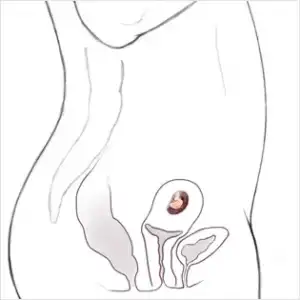

6.haftaya gırenlerrrrrrr bu hafta bebegınızde ki gelısımlerrrr

6 HAFTALIK GEBELİK (HAMİLELİK) GÖRÜNTÜSÜ

ALTINCI HAFTADA HAMİLELİK - BEBEĞİN BOYU, KİLOSU, BÜYÜKLÜĞÜ

Altı haftalık gebelikte bebeğin kalp atışları rahatlıkla ultrason muayenesinde duyulabilir ve görülebilir. Bebeğin boyu çok küçük 4-6 mm kadardır. Kilosundan bahsetmek henüz mümkün değildir. Bebeğin solunum ve sindirim sistemini oluşturacak ilk yapılar belirginleşir.

6. haftada bebeğin göbek kordonu oluşur. Gözler, kulaklar ve ağız boşluğu belirmeye başlar. Bebeğin beyni gelişmeye ve aktivite göstermeye başlamıştır. Bebeğin ileride kol ve bacaklarını oluşturacak tomurcuklar şimdiden belirginleşmeye başlar.